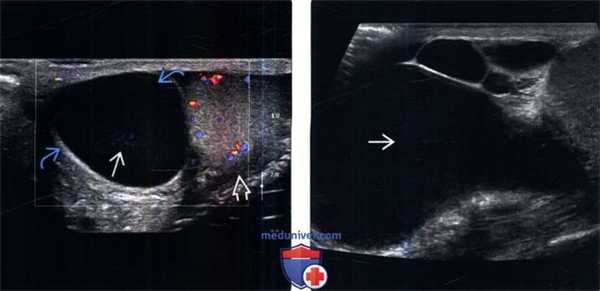

(Слева) УЗИ: крупное сперматоцеле в верхнем полюсе правого яичка, которое содержит точечные низкоуровневые эхо-сигналы с соответствующим артефак том на допплерографии. Эти точечные очаги подвижны.

(Справа) УЗИ, В-режим, в продольной плоскости: сложное кистозное образование со множеством перегородок и бесчисленными камерами, содержащими детрит. Данные признаки характерны для сперматоцеле.